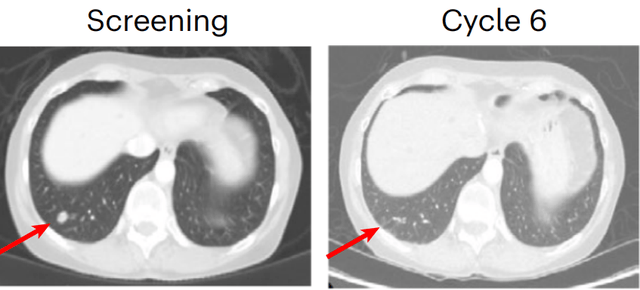

更加令人振奋的是,一名两次治疗失败的直肠癌患者,在联合治疗后,肺部肿瘤竟然完全消失不见!